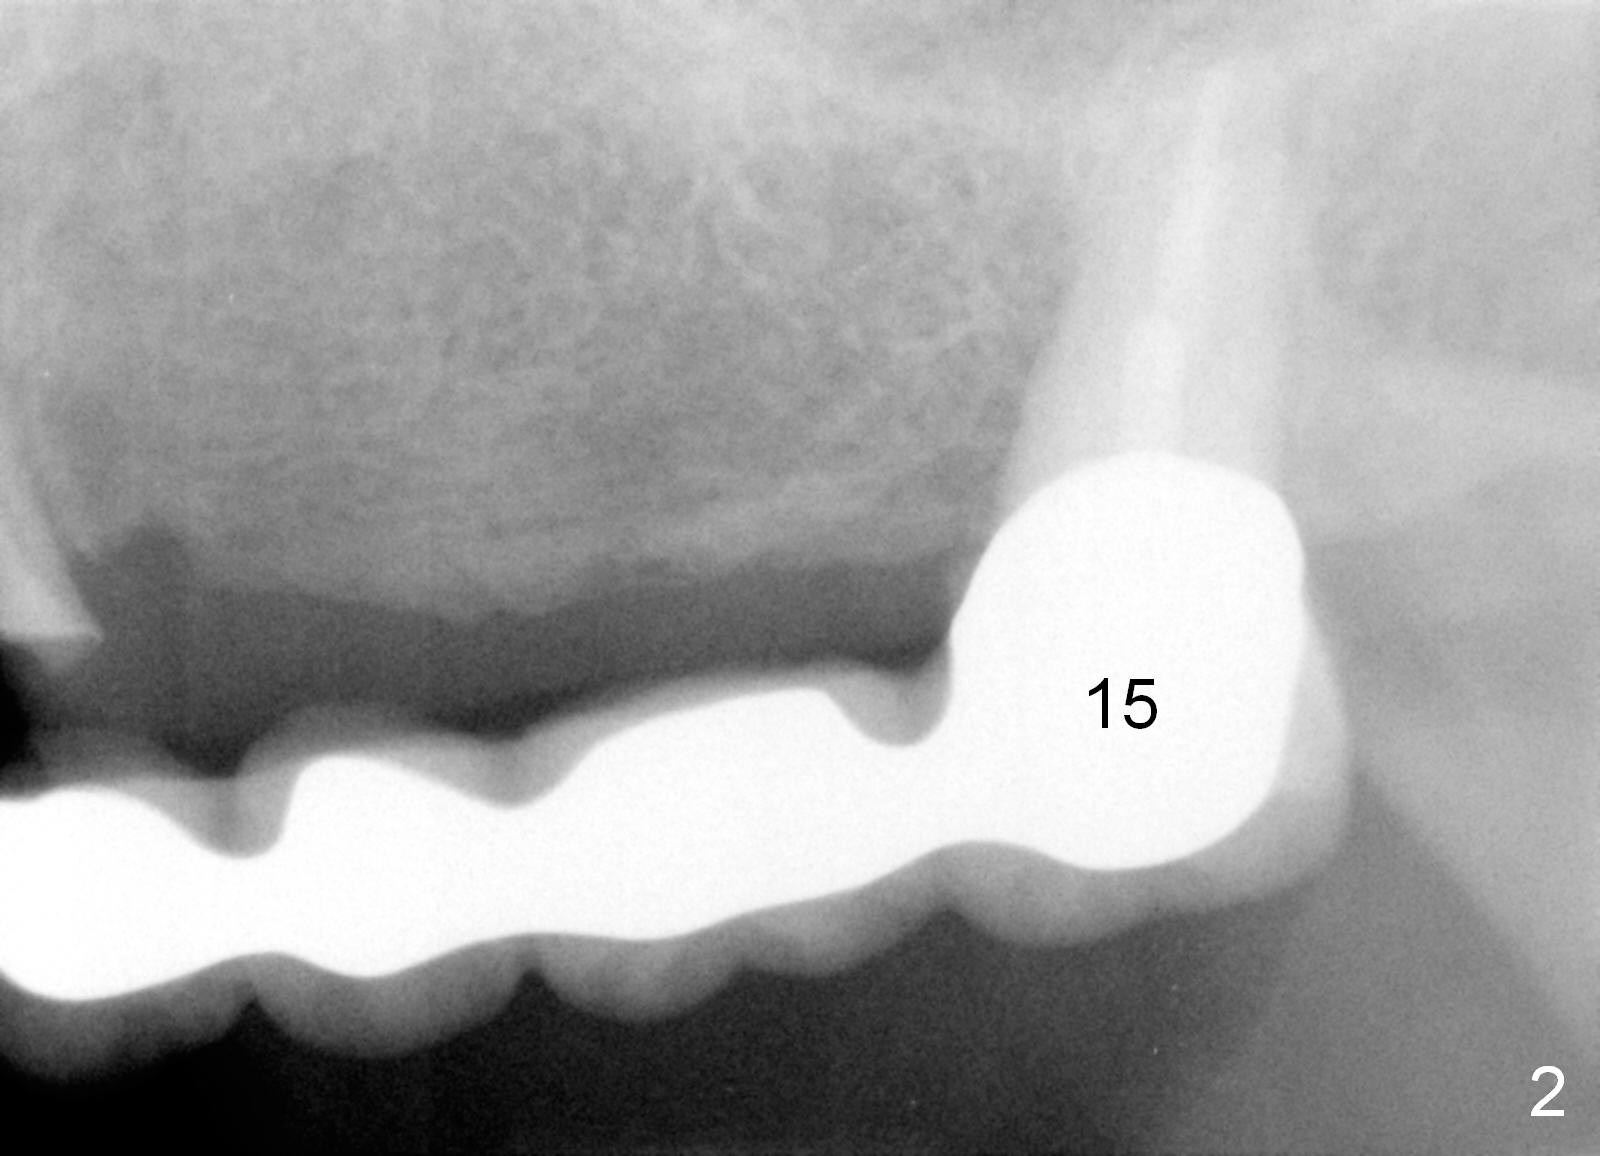

A 68-year-old female has had a long spanned FPD (fixed partial denture, bridge) for the last 2 years.  It is loose (Fig.1,2).  The patient is concerned about cosmetics, but has limited finance.  The FPD dislodges when Alginate impression is being taken.  The teeth #11 and 15 will be extracted and replaced immediately by implants (Fig.3,4).  After placement of abutments, a 5-unit immediate provisional FPD will be fabricated if the implants achieve primary stability.  Otherwise, an additional implant will be placed at the site of #13.  There will be no occlusal contact.